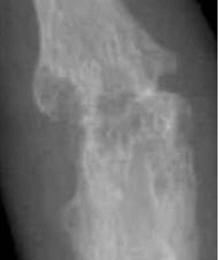

RA – Damaged fingers and wrist RA – Fused wrist bones

https://commons.wikimedia.org/wiki/File:Rheumatoid_arthritis_with_unaffected_carpal_bones_2009.jpg

| Description | English: X-ray of the wrist of a then 58 year old

woman with rheumatoid

arthritis, showing unaffected carpal bones. 8 years later,

she had developed ankylosing fusion of the bones - see File:Rheumatoid arthritis with carpal ankylosis

2017.jpg. |

https://commons.wikimedia.org/wiki/File:Rheumatoid_arthritis_with_carpal_ankylosis_2017.jpg

Description    English:

X-ray of the wrist of a 66 year old

woman with rheumatoid arthritis, showing ankylosing fusion of the carpal bones. Previous X-ray showed unaffected carpal bones - see File:Rheumatoid arthritis with unaffected carpal bones 2009.jpg.

Date               19 January 2017